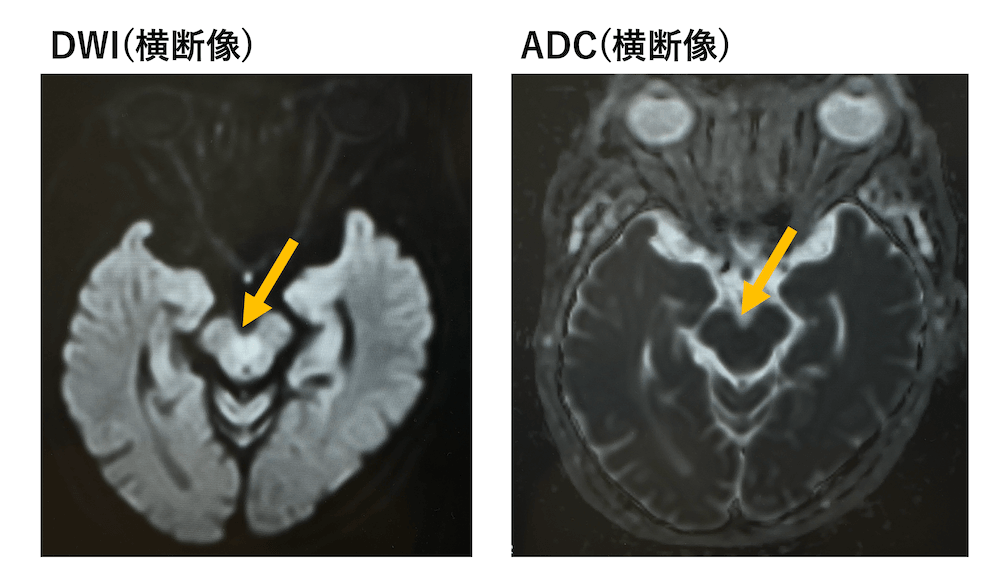

中脳被蓋(上小脳脚交叉)に左右対称なDWI高信号

DWIで中脳被蓋に対称性に高信号spotを認めますが、ADCでは周囲とほぼ等信号で、有意な信号低下を認めません。

正常な上小脳脚交叉の高信号を疑う所見で有意ではありません。